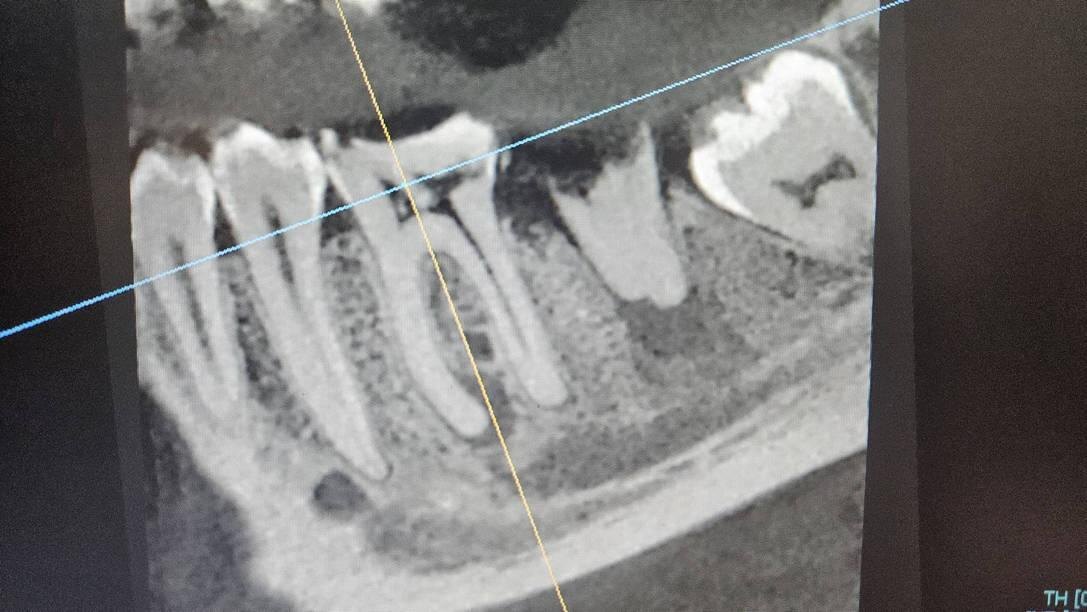

Зуб 3.7 давно разрушен, он не беспокоил Владимира, поэтому мужчина не спешил лечить его терапевтически или удалять. По результатам визуального осмотра, перкуссии и пальпации выяснили, что источниками боли являются два зуба: 3.6 и разрушенный 3.7. Для полного понимания ситуации в полости рта направили пациента на рентген📸

Источники острой боли: зубы 3.6 и 3.7